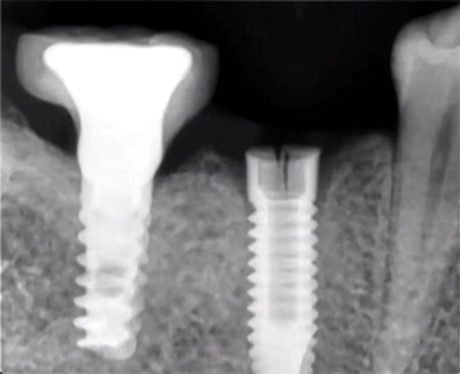

(8.) Mid-body fracture of a CP-Ti grade 4 implant related to overload and a longer fulcrum on the implant following bone loss.

Figure 8